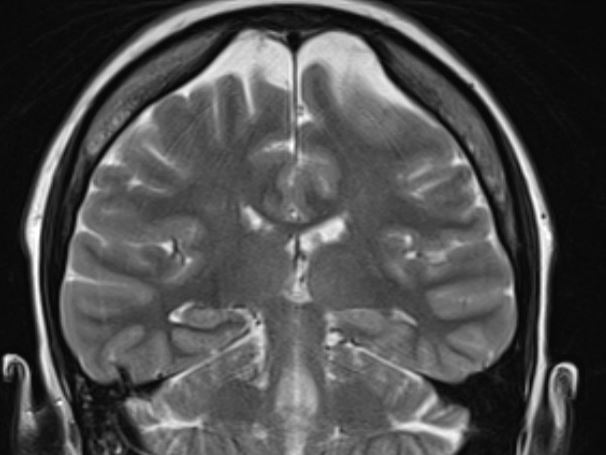

The structural correlates of the above EEG findings appear below. There is enlargement of the left-ventricular system, atrophy of the head, body and tail of the caudate nucleus and the left hemisphere appears modestly smaller in size than the right, most evident on axial sequences. The MRI was done while the patient was quite restless. As you can see from these pictures, the left occipital cortex and the left thalamus do not demonstrate any structural correlate to the asymmetry of alpha rhythms. However, we know from the EEG that the left hemisphere is markedly dysfunctional. Unsurprisingly, on functional MRI scans language is represented in the right hemisphere.